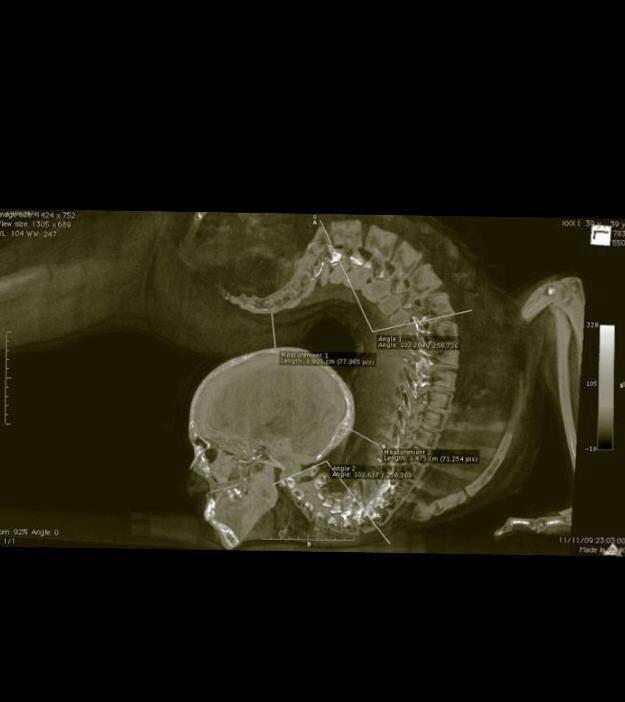

Ciąża w przekroju